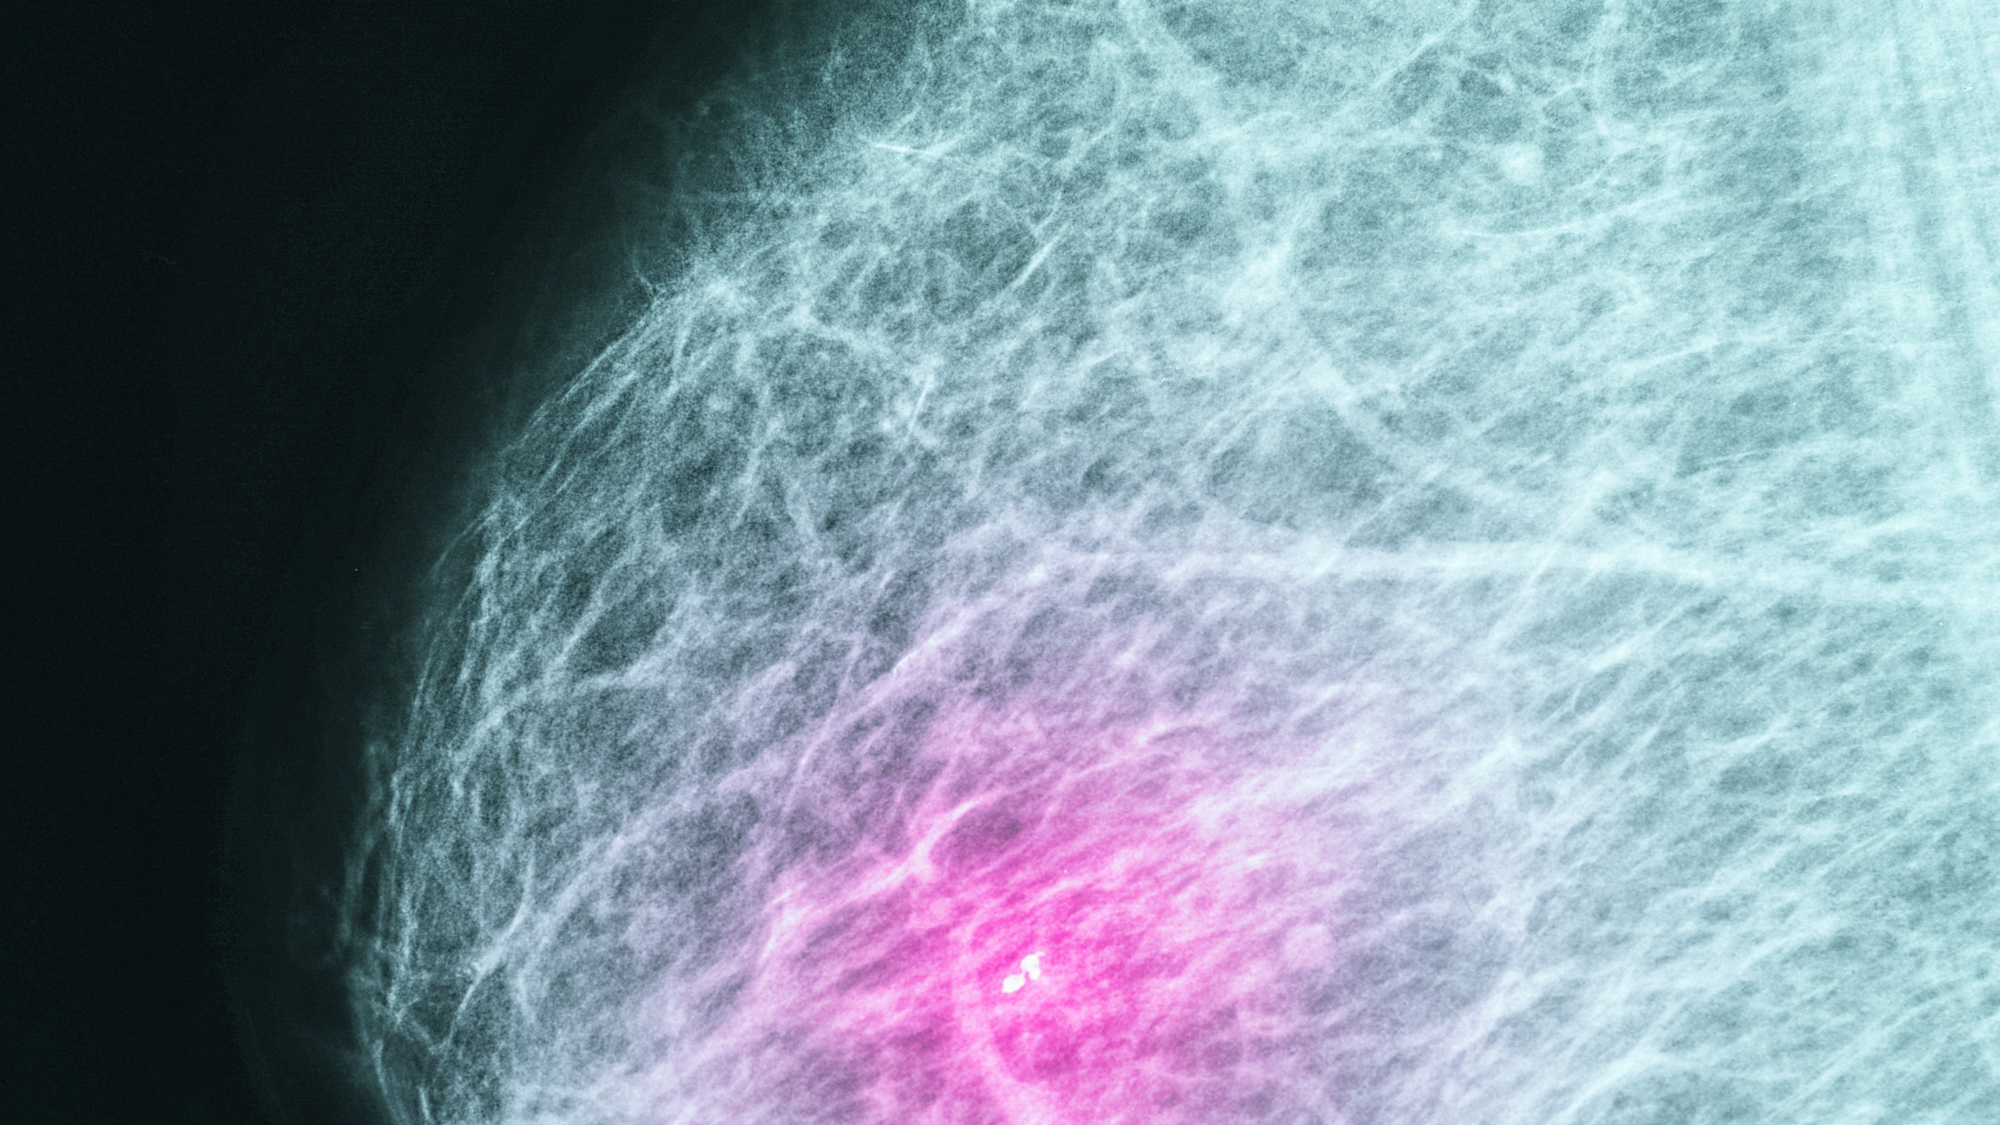

Breast cancer is the most common non-cutaneous cancer in women, and the leading cause of cancer death in women age 40–65. Missed, delayed or wrong diagnosis of breast cancer is a leading cause of malpractice claims, especially in young women. This talk, titled “Breast Care Risk Assessment Among Women 40–49 in Primary Care,” was presented in June 2019 as part of a patient safety grant program sponsored by CRICO/Risk Management Foundation of the Harvard Medical Institutions.